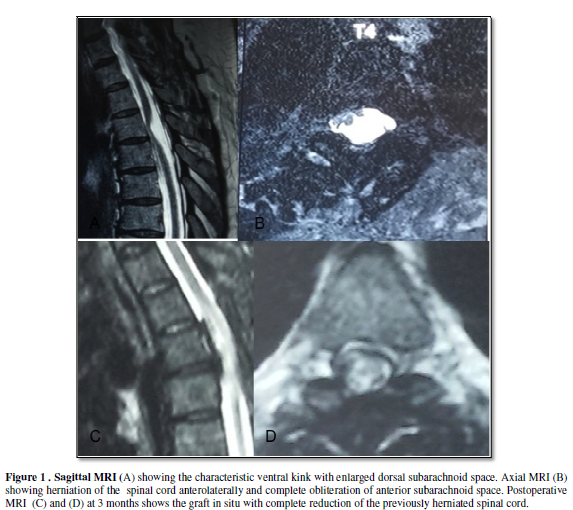

of T4. MRI of the dorsal spine

suggested an anterior displacement of the spinal cord with a characteristic

kink (Figure 1).

The herniated spinal cord was seen in the axial MRI. With the patient

with significant improvement in her sensory perception. Her postop MRI showed

complete reduction of the herniated cord (Figure

1).